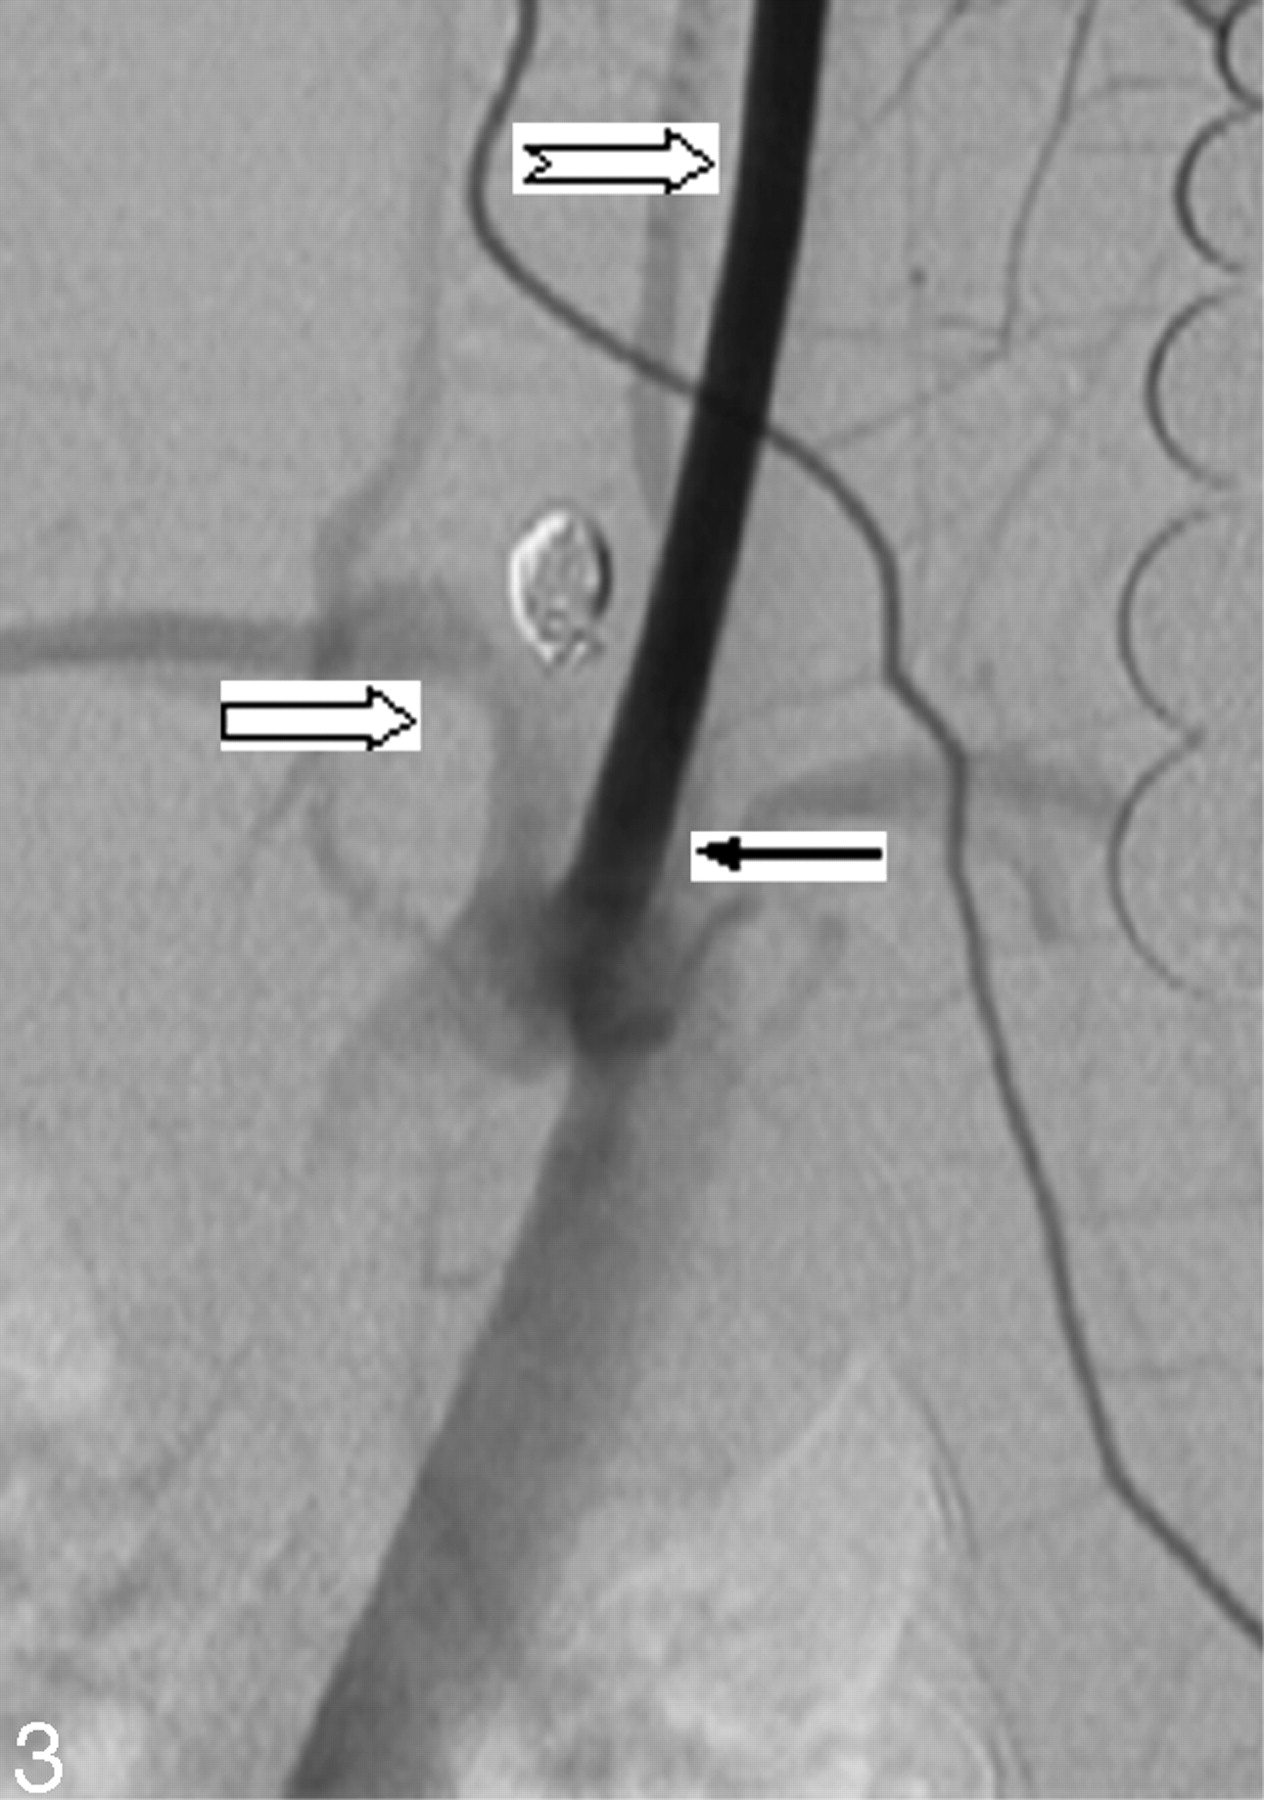

Twenty-eight (82%) of the 34 cases were considered grade A, or good, image quality (Fig 2). Six (18%) of 34 aneurysms were judged grade B, or poor, image quality. Of these 6 cases, 2 had poor opacification of the aneurysm neck region, 3 had poor opacification of the parent artery, and 1 had poor opacification of both the parent artery and neck region (Fig 3).

IADSA through the left ear artery. Both embolized aneurysm and parent artery (right block arrow) are not well shown. Note that the LCCA (notched right arrow) is seriously opacified. On the contrary, the parent artery is very faint. LCCA and RCCA, originating separately from the aorta (black arrow).

There were 2 types of vessel origination: type A, with a common origin for the RCCA and LCCA; and type B, with separate origins of the RCCA and LCCA from the aortic arch. All 28 aneurysms with grade A image quality had type A anatomic configuration (Fig 2). In all 6 cases with poor opacification (grade B), anatomic configuration type B was shown (Fig 3).